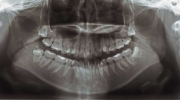

| 初診時

|